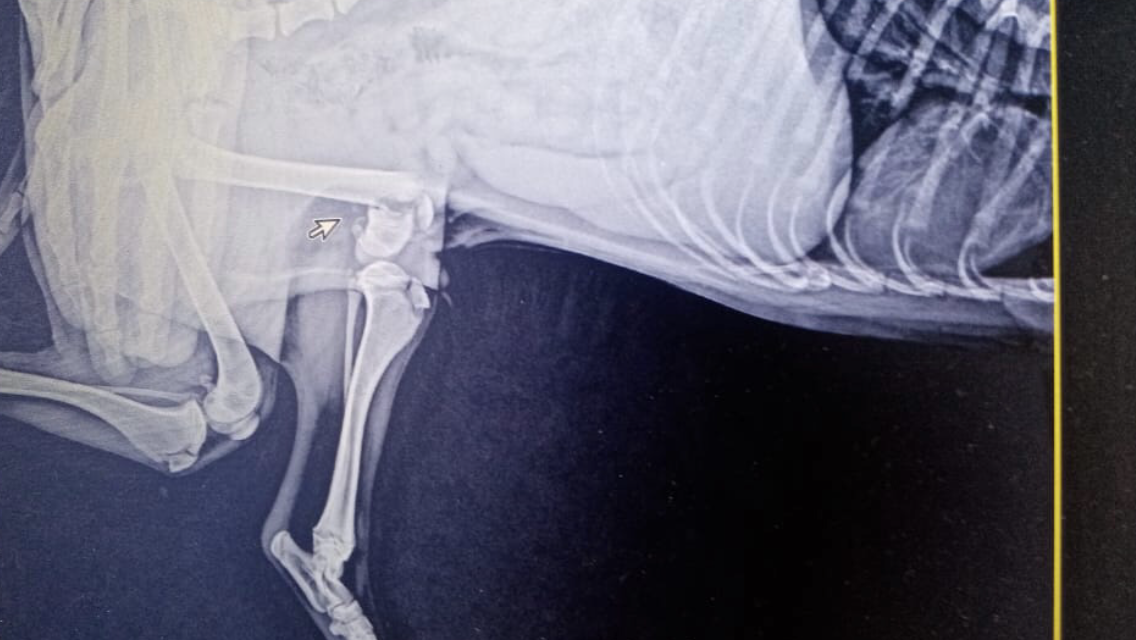

Пострадавший Гонзо

Щенок 4-5 месяцев. Снимки подтвердили сложный перелом бедренной кости. А ещё обнаружен пироплазмоз, на ранней стадии.

Завтра осмотр хирурга. О принятом решении врача - сообщу.

Уже проведена операция, операция прошла успешно и на следующий день забрали Гонзо из клиники, нет у нас возможности оплачивать стационар, будем выхаживать дома. Пироплазмоз вылечен, на ранней стадии лечится быстро.